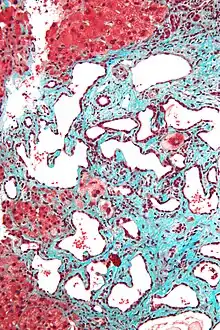

Micrograph of a bile duct hamartoma. Trichrome stain. Intermediate magnification Micrograph of a bile duct hamartoma. Trichrome stain. Intermediate magnification